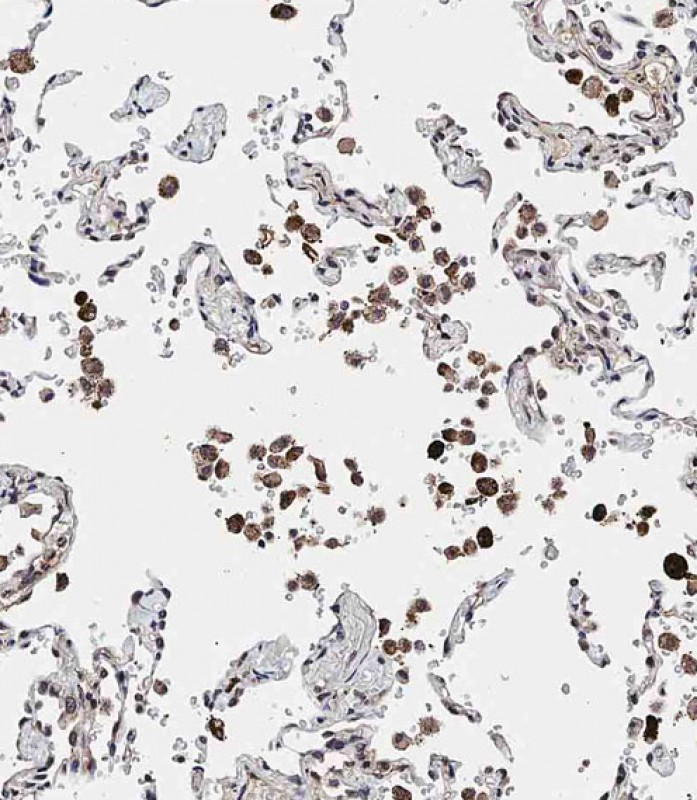

IHC 1/100 Human,Mouse,Rat

ADAMTS17 antibodies, typically polyclonal or monoclonal, are generated in hosts like rabbits or mice using immunogenic peptide sequences. They enable protein detection via techniques such as Western blotting, immunohistochemistry (IHC), or immunofluorescence (IF). These antibodies aid in studying ADAMTS17's tissue distribution (e.g., in eyes, heart, skeletal tissues), expression patterns during development, and dysregulation in diseases. Recent studies also explore its potential as a biomarker or therapeutic target. Validation includes specificity checks using knockout controls or siRNA knockdown. Researchers use these tools to unravel ADAMTS17's biological functions, interactions with ECM components like fibrillin-1. and contributions to connective tissue pathologies.